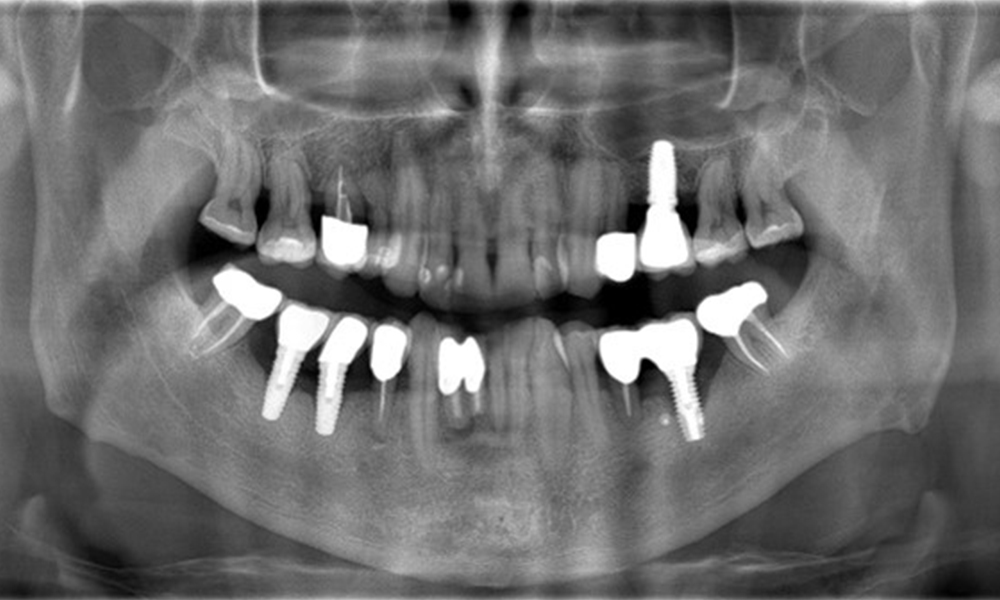

The X-ray images show the progression of bone loss.

The X-ray images show the progression of bone loss. OPG from 29.06.2020 (left) and OPG from 26.02.2024 (right).